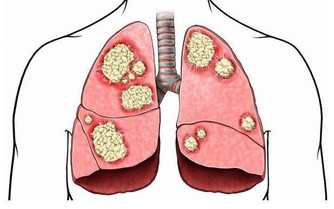

七、防治感冒,祛寒暖身;